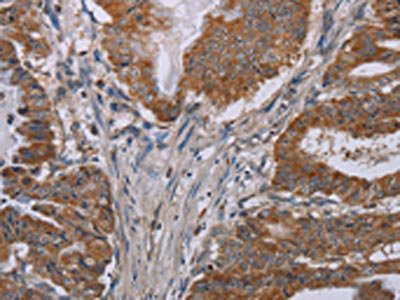

The image on the left is immunohistochemistry of paraffin-embedded Human brain tissue using CSB-PA655952(NOX3 Antibody) at dilution 1/40, on the right is treated with synthetic peptide. (Original magnification: ×200)

The image on the left is immunohistochemistry of paraffin-embedded Human esophagus cancer tissue using CSB-PA655952(NOX3 Antibody) at dilution 1/40, on the right is treated with synthetic peptide. (Original magnification: ×200)